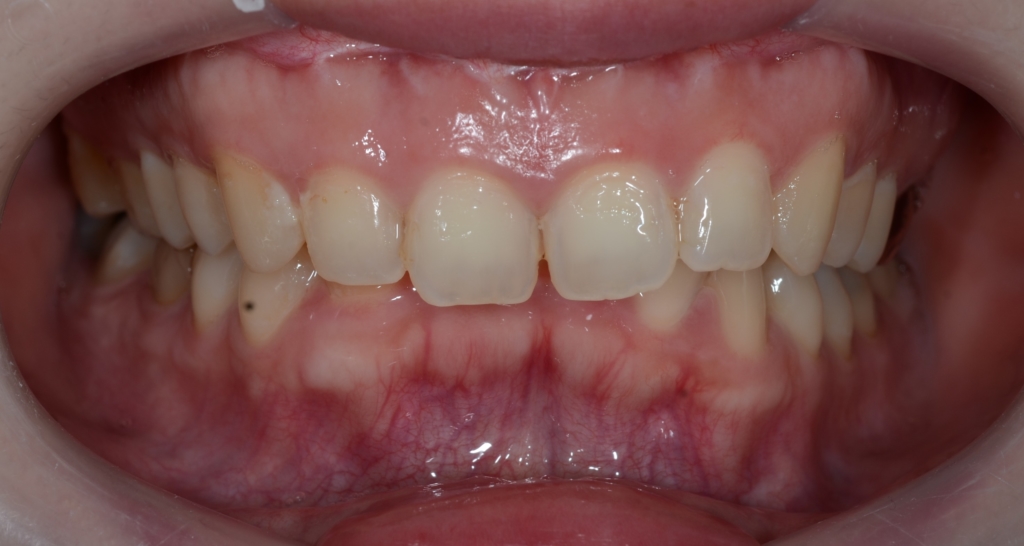

【Before】

【診断】

#1.上顎前突

#2.ガミースマイル(重度の過蓋咬合を伴う)

と診断しました。

補足:口腔前庭縮小術の既往あり(美容外科にて)